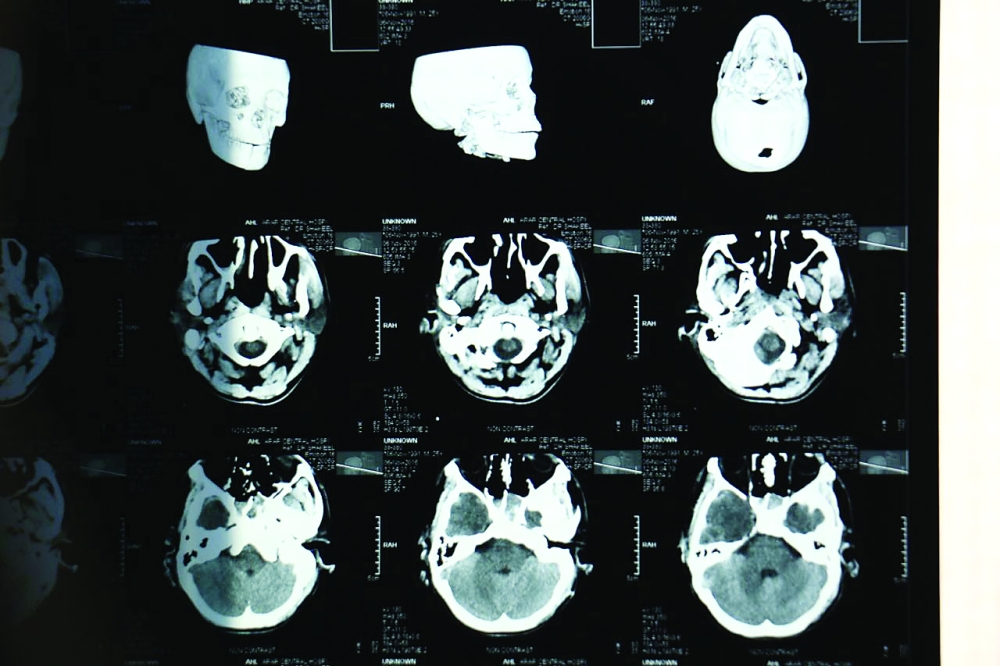

صورة أشعة لجمجمة المصاب.

تمكن فريق طبي في مستشفى عرعر المركزي أخيرا، من إنقاذ حياة مقيم سوداني، تعرض لحالة دهس، نجم عنه انتفاخ واحتشاء نزفي شديد بالمخ، وكسر بالجمجمة والفك، إضافة إلى انحراف شديد للخط الناصف للمخ، وكسر بكامل القدم اليسرى، وضياع جلدي في الجهة اليمنى بالوجه.

وأجرى الفريق الطبي بقيادة استشاري جراحة المخ والأعصاب عملية خزع جمجمة طارئ والاحتفاظ بجزء من عظم الجمجمة في جدار البطن، وذلك للسماح بتمدد أنسجة المخ خارج تجويف الجمجمة وتقليل الضغط داخل المخ، فيما تم إجراء عمليه ثانية للمريض بعد استقرار حالته الصحية وهي تجميلية بالوجه للجهة المتضررة.

كما خضع المريض لعملية جراحية ثالثة لإعادة تثبيت عظم الجمجمة في مكانه، إذ تم متابعته ومراقبته إلى أن تحسنت حالته الصحية وسمح له بالخروج من المستشفى وهو بصحة جيدة.